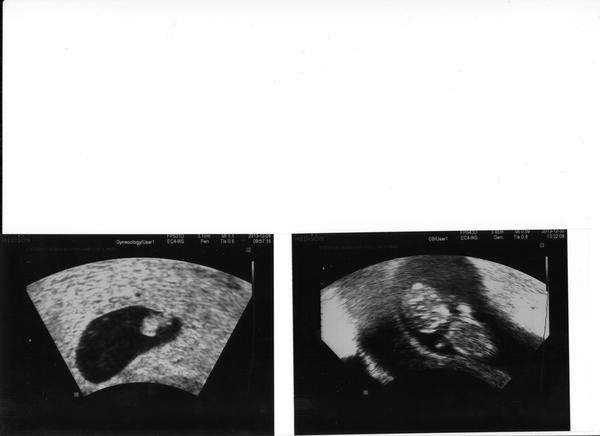

Ahojky holky, jsem se tu dlouho neukázala, také přispěju. Nevím, čím začít. Pěkně přibírám cca 5kg a to jsem ve 12 týdnu a to se nepřecpávám. Už tři týdny bojuju s rýmou, jsem z toho nešťastná.Během dne dýchám pusou a v noci si musím stříknout Otrivin, vím, že se to nesmí, ale jinak bych se nevyspala, takhle chrním pěkně až do rána, teda pokud mě nebudí kocour 🙂 30. prosince jsem byla na kontrole, vše je v pořádku, prcek roste má 4 cm, pěkně tam sebou mrcasil i slzičky ukáply, no prostě nádhera. 14. ledna jedeme na nt screening do Brna a s tím souvisí má otázka, co mne tam čeká? Ultrazvuk se dělá přes bříško nebo vaginálně?

@velkaverca Většinou stačí přes břišní stěnu.Ale je možný že budeš mít horší viditelnost.Mě si pozvaly znova v 16 tt pač mám vpředu i placentu tak to bylo míň vidět.Vnitřní nedělal vůbec.Dával mi poslechnout i srcíčko a je to ten nejkrásnější zvuk co jsem kdy slyšela. 😉 Držím palce ať je mimi vpořádku. 🙂

@velkaverca já byla na 1 screeningu v Praze v té době jsem měla 118 kg a mimísek byl krásně vidět, vše nám ukázala,vysvětlila,byla jsem spokojená a manžel tam semnou byl..někdo se na pohlaví ptá a i jim to lékař řekne... mi se neptali, chcem to vědět,ale zeptáme se až na 2 screeningu ve 20 týdnu

@velkaverca jj to teda lepší UTZ MAJÍ JE TO KRÁSNĚ VIDĚT..... ten náš miláček se tam tak strašně mrskal. ručičkama tam šermoval... krásnýý to bylo...

@whitelilith Už se nemůžu dočkat, až mrně poprvé ucítím, že tam je. Taky jsem přestala kouřit, proto možná tak přibírám, ještě k tomu svátky a mimi a je vymalováno, ale cítím se dobře, teda až na ten ucpanej nos. Jinak manžel přibral víc než já, taky přestal kouřit, jsem na něj pyšná.Snad to vydrží. Posílám fota v 7 tt a v 11 tt